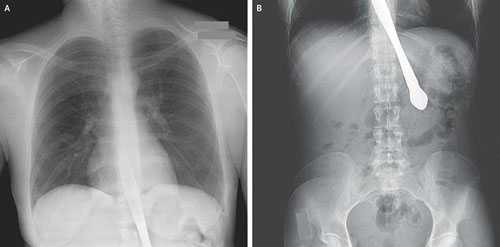

Tạp chí Y học New England số ra tháng 8 vừa đăng hình chụp X-quang một con dao găm vào thực quản người phụ nữ 30 tuổi do nuốt phải dao thái bơ.

| Hình chụp con dao kẹt trong cổ họng người phụ nữ 30 tuổi. Nguồn: Tạp chí Y học New England |

Người phụ nữ liều lĩnh trên được đưa đến phòng cấp cứu của Trường Đại học Y Emory ở Atlanta (Mỹ) trong tình trạng đau ngực, nôn ra máu. Các bác sĩ đã mổ nội soi, lấy ra con dao để cứu sống bệnh nhân.